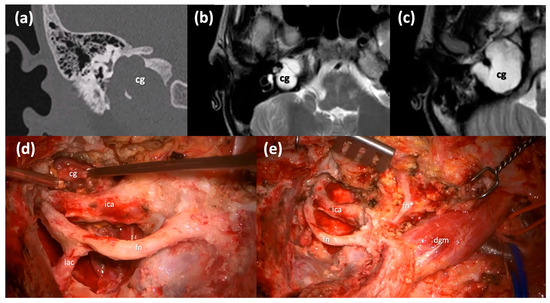

The Type B infratemporal fossa route in combination with a transotic one is selected in case of a pre-operative severe-profound sensorineural hearing impairment since it sacrifices the hearing function, and it requires the blind closure of the external auditory skin. This technique is based on the skeletonization of the facial nerve, which is kept suspended in its bone canal from the stylomastoid foramen to the fundus of IAC, and on the skeletonization of the intrapetrous ICA in its vertical and horizontal portions. This is possible through the anterior transposition of the mandibular condyle and the middle meningeal artery and the V3 trigeminal branch section, to allow for the control of the horizontal portion of the intrapetrous ICA. This approach allows for the removal of the lesion with its capsule from the petrous apex to the clivus anterior to the ICA (Figure 4), while allowing for a direct visualization and a complete control of the whole intrapetrous ICA. Once the cholesterol granuloma has been removed, the surgical cavity is filled with abdominal fat.

Figure 4.

Type B infratemporal fossa approach combined with a transotic approach. (a) Coronal CT scan of a massive right Type C PACG. (b,c) Axial T2-weighted MRI sections of the same PACG showing its hyperintense signal and its relationship with the IAC, the ICA and the clivus. (d) Surgical step: the facial nerve has been completely skeletonized from the IAC to the stylomastoid foramen and it is left in a bridge-like fashion over the surgical field; careful maneuvers are employed to dethatch the PACG from the horizontal segment of the ICA. (e) Surgical step: final surgical field where the PACG has been completely removed. cg, cholesterol granuloma; ica, internal carotid artery; fn, mastoid segment of the facial nerve; iac, internal auditory canal; fn*, intraparotid facial nerve; dgm, digastric muscle.

This route is suggested if the cholesterol granuloma has a significant extension, and it is closely related to the intrapetrous ICA. In all the cases of intrapetrous ICA involvement, the surgeon must take into account the necessity for a detailed radiological preoperative study of the vessels [8].